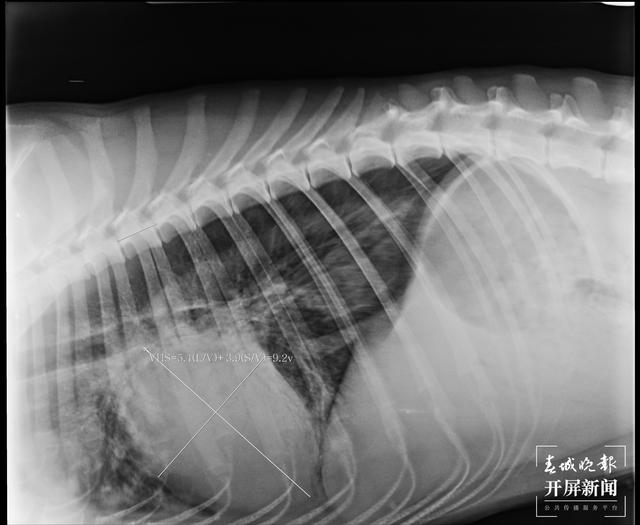

2月22日,CT显示心脏肿大。(受访者供图)